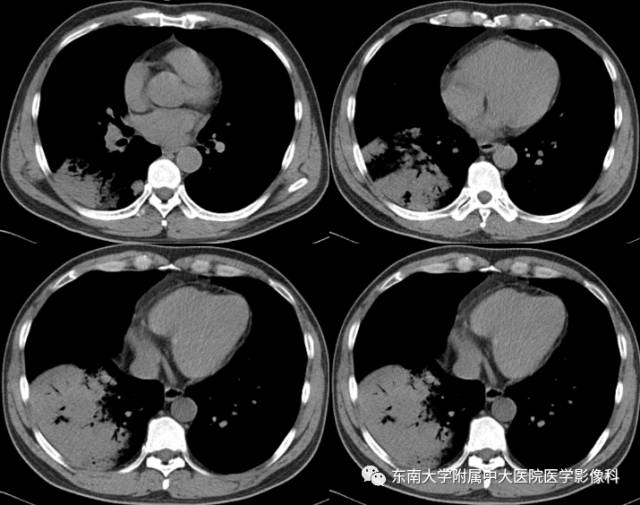

2015-10-08 入院CT